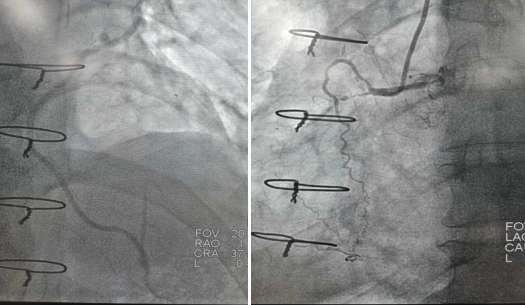

2022年9月16日行冠脈造影術,造影結果示:左主干末端99%狹窄,LAD近段100%閉塞,LCX開口及近段95%狹窄,乳內動脈-左前降支血管通暢,RCA近段100%閉塞,大隱靜脈橋血管未見,考慮閉塞。

心血管病院吳棟梁院長、CCU李新國副主任、心血管內科二病區趙娟副主任、王端樂主治醫師、宋睿主治醫師介入團隊造影后認真研究患者的病情和影像資料,決定開通閉塞長達11年的右冠狀動脈,精確選擇器械,選擇同軸性及支撐力均好的指引導管,術中選用微導管輔助,軟、硬導絲結合等技術,聚精會神、揮汗如雨,終于歷經3小時的努力,成功前向開通右冠狀動脈,精準選擇由遠及近“鋪設”通過性較好、長度合適的支架 。

(術前術后對比)

術后癥狀明顯改善,活動后無胸悶、胸痛,明顯提高患者生活質量,提高患者生存率,使患者絕地逢生。